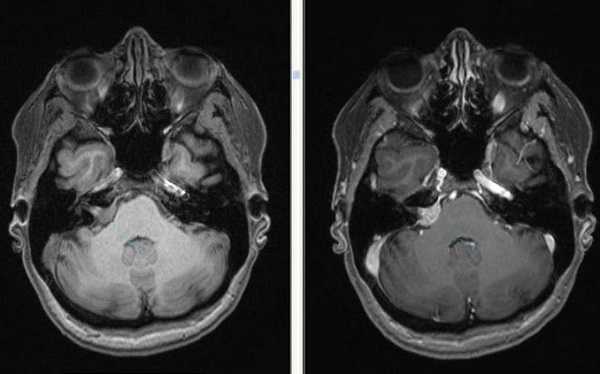

МРТ головного мозга. На мрт в аксиальной плоскости отмечается объемное образование внутреннего слухового прохода слева (стрелка), с четкими и неровными контурами, деформирующее окружающие структуры. После внутривенного введения парамагнитного контрастного вещества отмечается интенсивное и неоднородное его накопление образованием (изображение справа) — невринома.